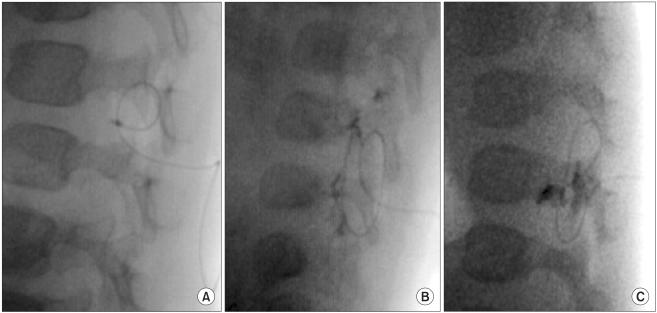

Seventy-five children were randomly allocated to 3 groups according to the epidural catheter insertion site (L2-3, L3-4, and L4-5). The epidural catheter tip was identified using 50% diluted Iohexol and fluoroscopy. The incidence of correct position was compared among the groups and between infants and children.

The incidence of correct position was significantly higher in the L2-3 group as compared to the L3-4 and L4-5 groups (P = 0.023 and P = 0.046 respectively). The incidence of correct position was higher in infants compared to children (P = 0.017).